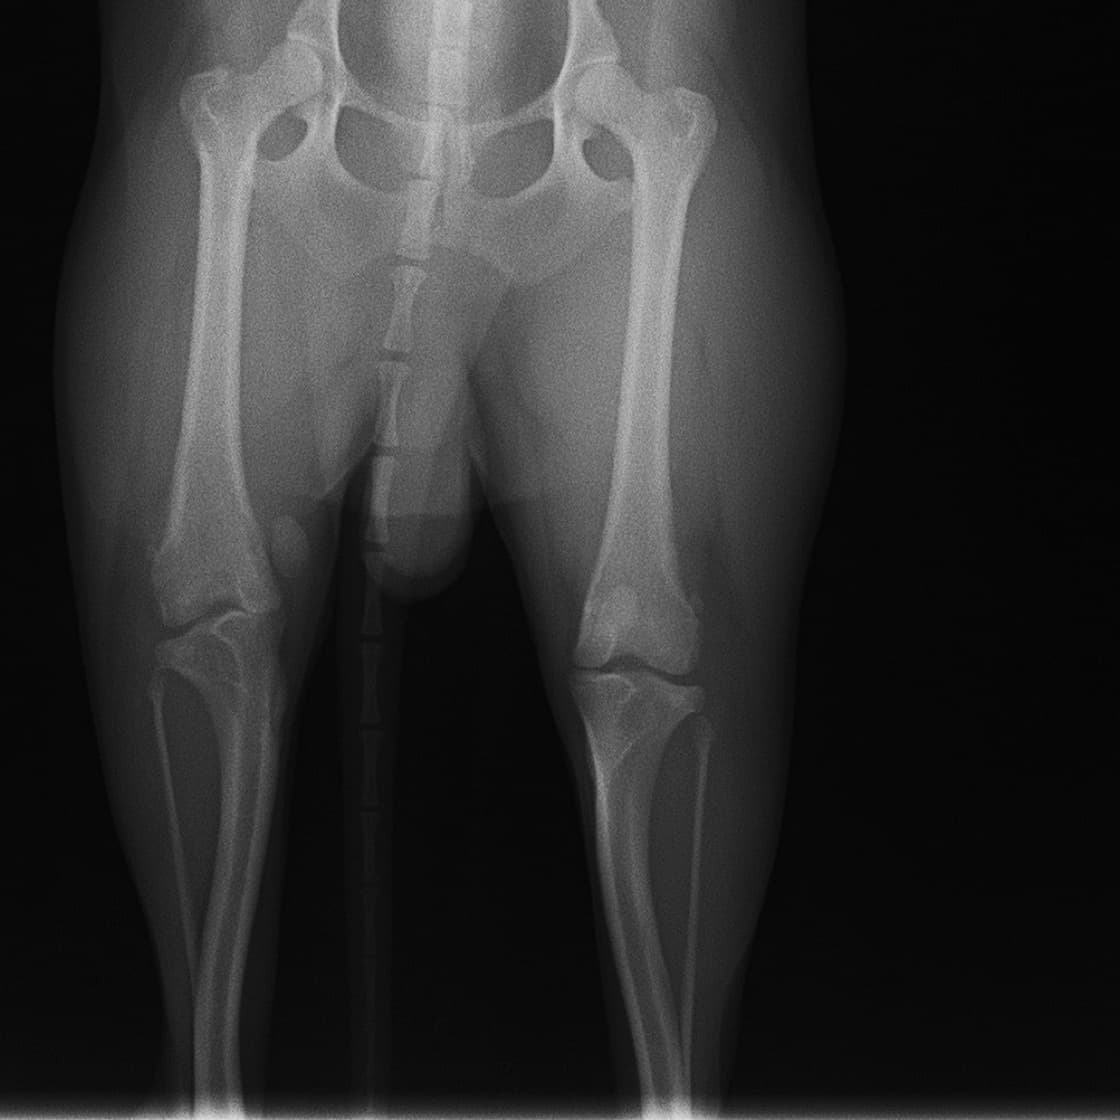

■ 症例24 キャバリア 7か月

左右膝蓋骨内方脱臼(左:グレードⅣ 右:グレードⅢ)

以前から左右後肢の跛行が認められ、整形外科学的検査・レントゲン検査により左右の膝蓋骨脱臼が認められた。症状が重度である左膝の膝蓋骨脱臼整復術を行った。外科手技は縫工筋及び内側広筋の解放、脛骨粗面の外側転位、滑車ブロック形造溝術、内外側関節方の縫縮を実施した。術後一か月時点で、左の膝蓋骨は安定しており経過は良好である。

本症例は成長期における重度の膝蓋骨脱臼であり、術後の再発の可能性もあるため、経過をしっかりと観察していく必要がある。また、今回手術を実施していない右膝に関しても経過を観察し、手術を検討していくこととする。